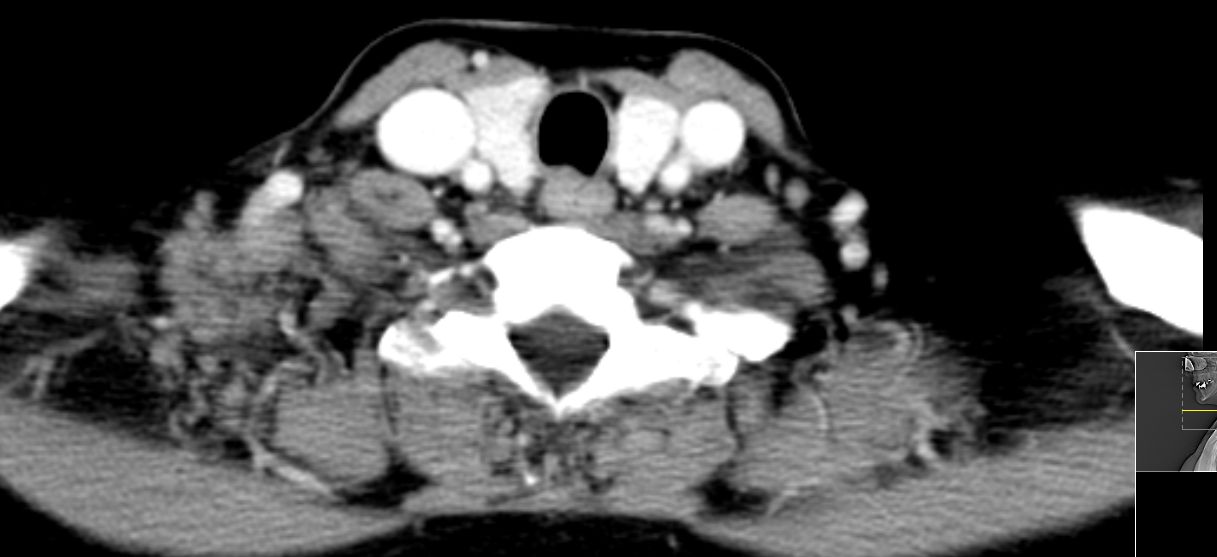

52-jährige Frau, bei der vor einem Jahr ein 15 mm großes invasiv-duktales Mammakarzinom rechts o/iq nach 3 Wochen Letrezol (Adapt-Studie) operiert wurde. Postoperativ ypT1c, ypN0 (0/2 sn), cM0, L1 V0 R0, G2, ER: 6/12, PR: 0/12, HER-2/neu: negativ, Ki-67: 30%, Oncotype DX Recurrence Score 40. CHT: 8 x nabPaclitaxel -> 4 x EC. Dann Bestrahlung der Brust. AHT mit Letrozol. Jetzt palpable Lymphknotenmetastasen supraklavikulär rechts. CT: Die teilweise rechts retroklavikulär hinter der rechten medialen Klavikula und supraklavikulär gelegenen Lymphknotenmetastase hat eine Größe von maximal 2,5 cm. Weiter oberhalb und dorsalseitig sind im rechten unteren Halsdreieck dorsal der rechten Vena jugularis externa konfluierende inhomogene Lymphknoten mit Einzelgrößen bis zu 1,5 cm und einer Gesamtpaketausdehnung bis zu 4 cm sichtbar. | ||